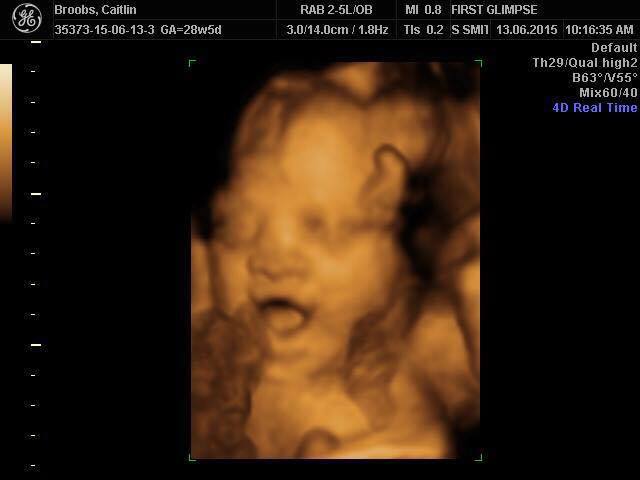

This is my first grandchild, Ava Haf. In 3-D.